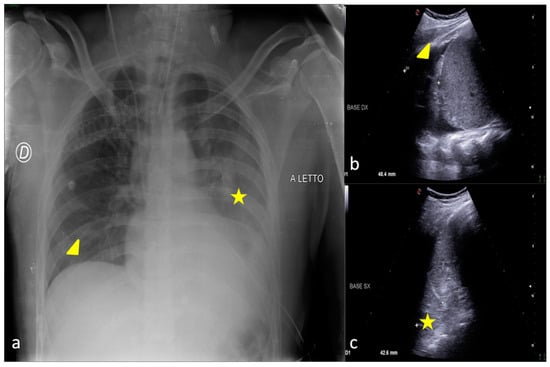

2.3. Pleural Effusion